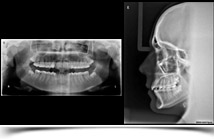

Nos permite la exploración detallada de los huesos maxilares y su relación con las estructuras faciales. Se utilizan en implantología oral, ortodoncia y cirugía para realizar diagnósticos y estudios detallados así como proyecciones radiográficas de todo el cráneo en una única imagen digital.